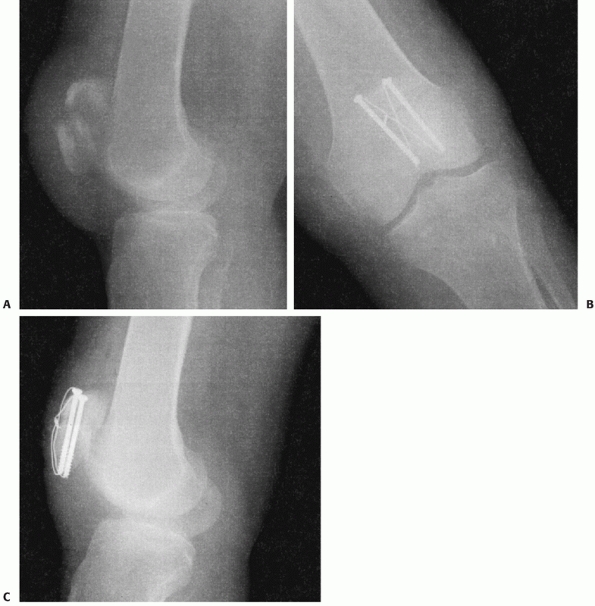

![]() |

|

FIGURE 52-10 Modified tension band wiring through cannulated screws. Lateral view (A) of injury. Anteroposterior (B) and lateral (C) views of internal fixation.

of clot and devitalized debris. In the setting of transverse fracture

patterns, we prefer a modified anterior tension band wiring and

cannulated screw construct (Fig. 52-10). With